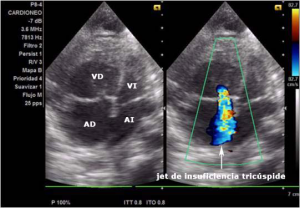

Doppler color

Es una variante del Doppler pulsado en la que se asigna un color al desplazamiento de la sangre en función de su dirección, rojo cuando se acerca al transductor, azul cuando se aleja, amarillo cuando se acerca con aceleración o turquesa cuando se aleja acelerado. Sirve para medición de regurgitaciones y estenosis a nivel valvular o vasos

Con el Doppler color se pueden cuantificar regurgitaciones valvulares, a nivel válvulas aurículo-ventricular (mitral o tricuspidea) o a nivel válvulas semilunares (aórtica y pulmonar). En este foto la punta cardiaca está superior.

La cuantificación del chorro regurgitante se debe realizar en varias proyecciones, teniendo en cuenta que son normales mínimas o leves regurgitaciones

El chorro de la regurgitación dependerá del tamaño del defecto de cierre (vena contracta) y genera un área de regurgitación (mayor cuanto mayor sea el tamaño de la vena contracta